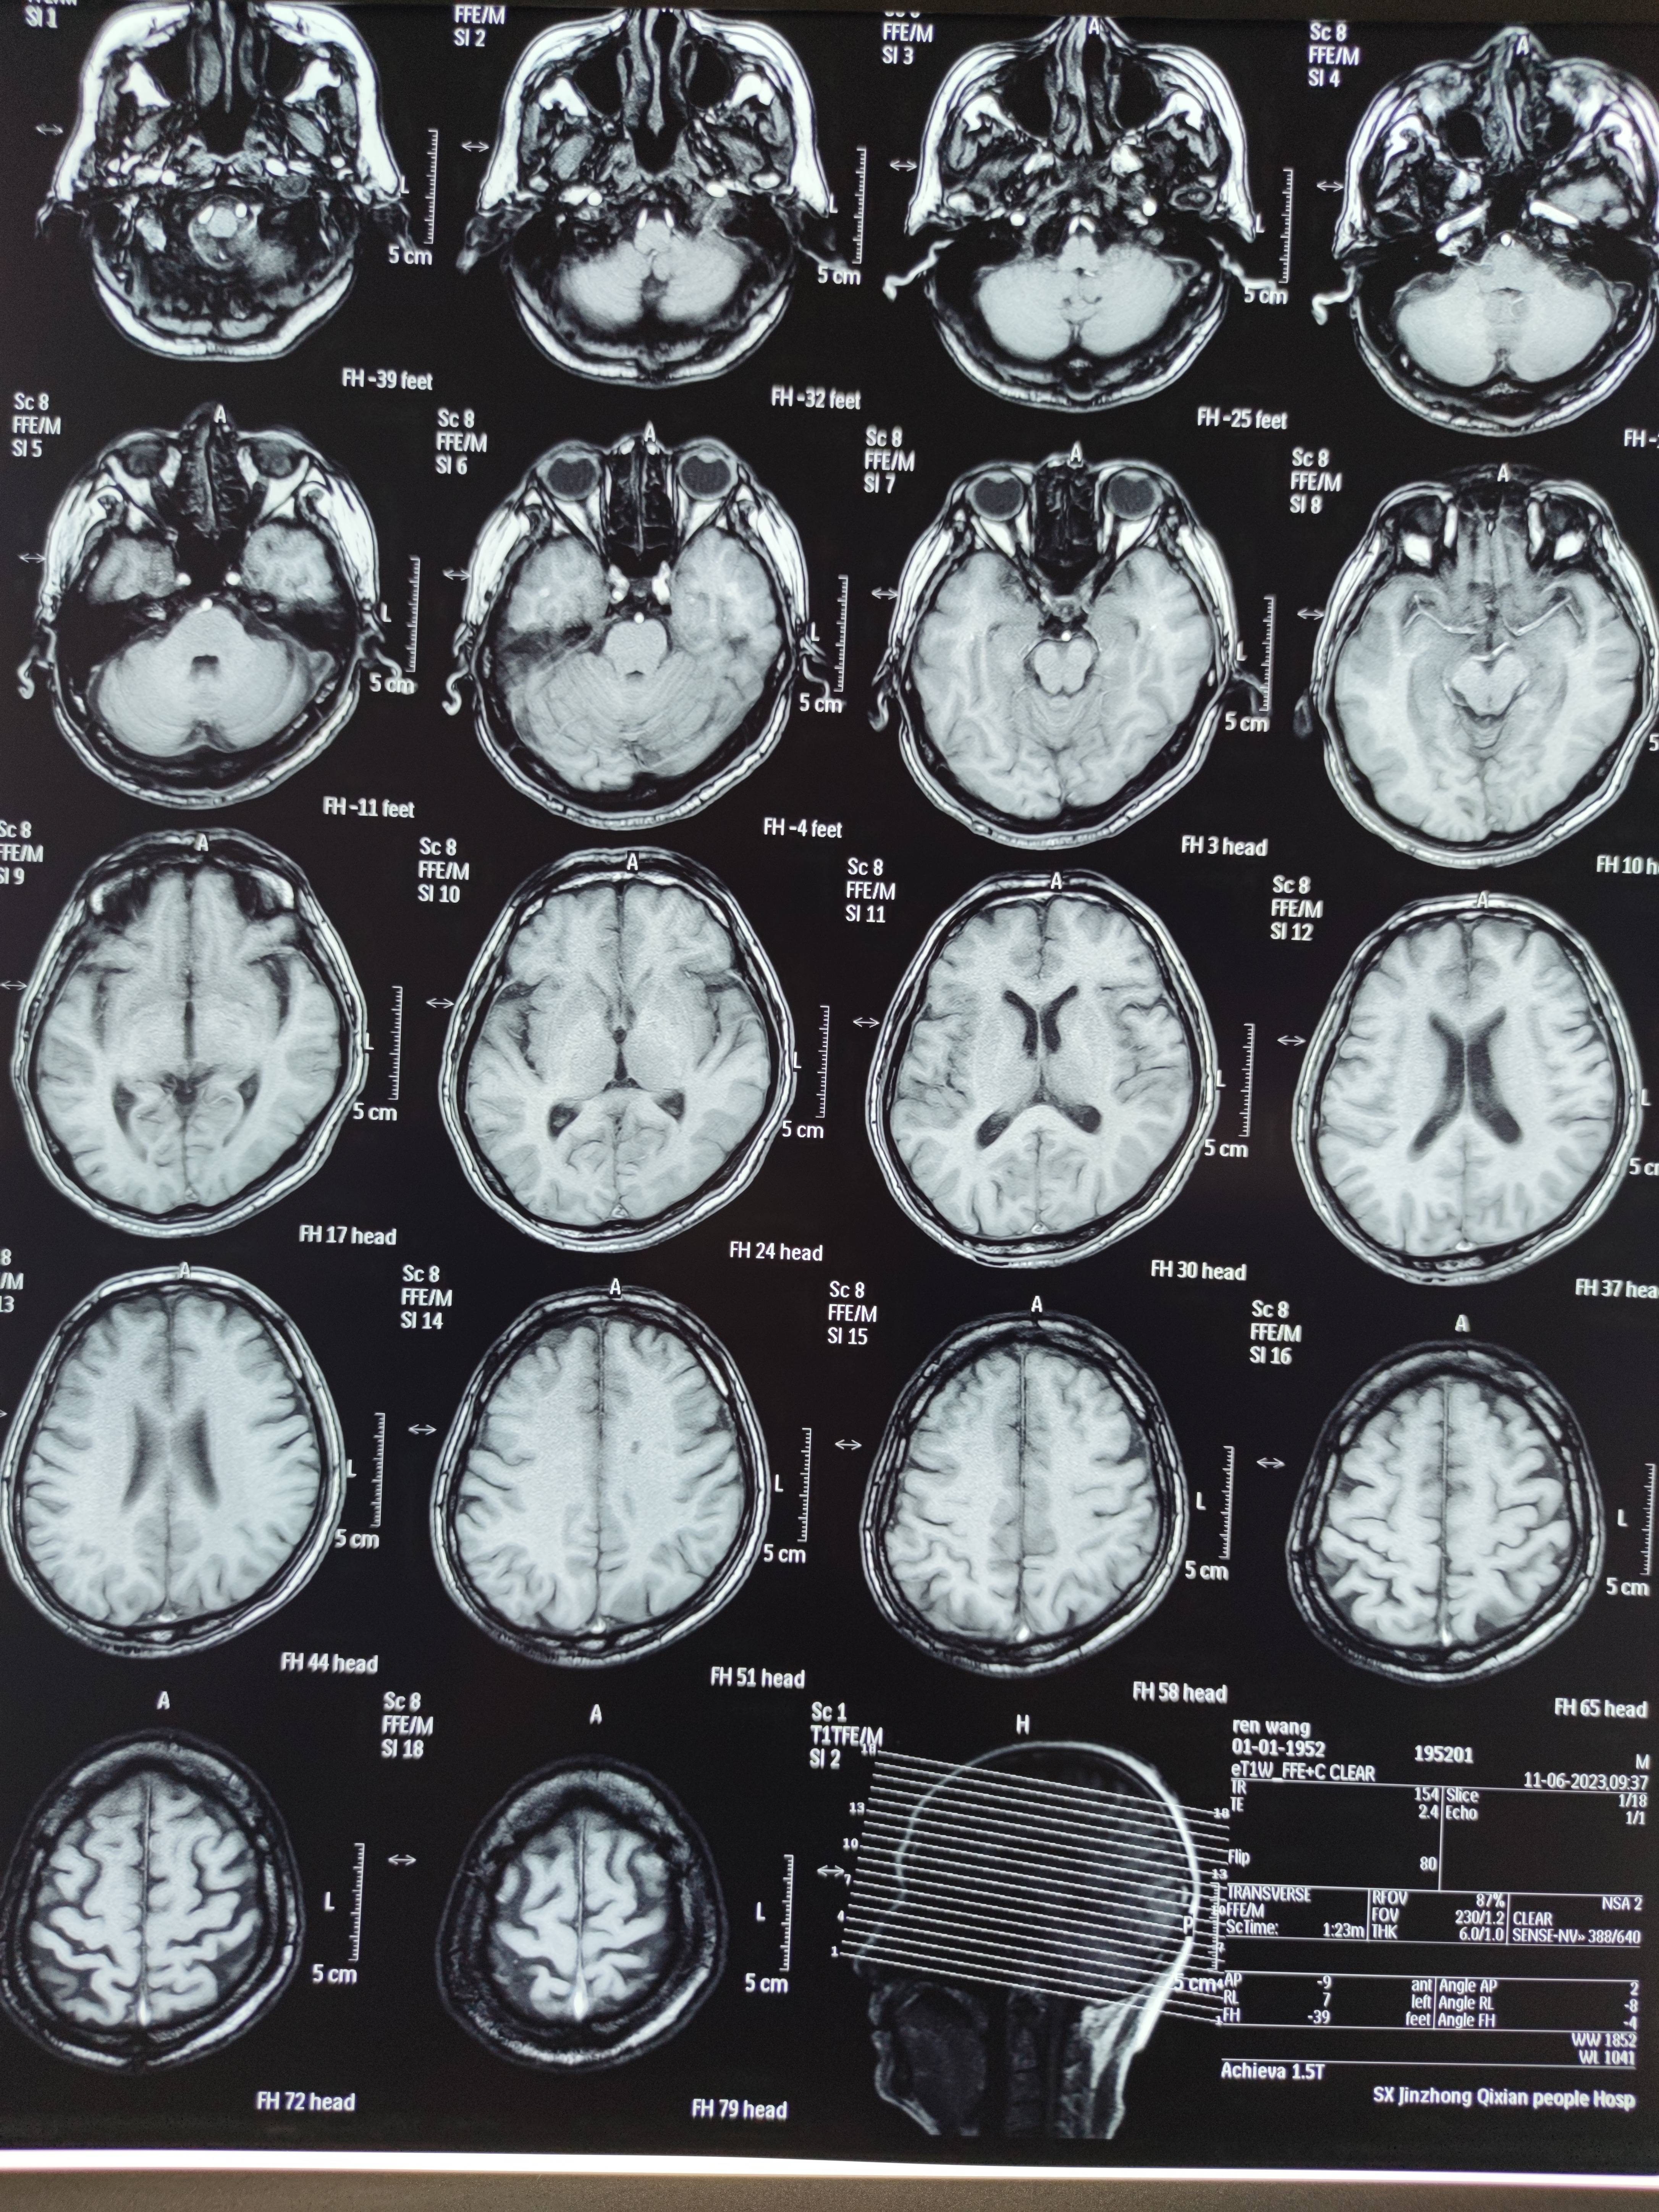

四月份癌胚抗原还是5.6,这个月到8了,持续升高。做了核磁增强,左侧桥小脑角哪有个地方不确定。肝脏核磁平扫弥散有两个点状高信号,转移也排不了,胃肠镜正常,左颈部有个变圆的淋巴结,保险点是不该加个化疗药了?咨询了陈波主任,等结果的吧!图片